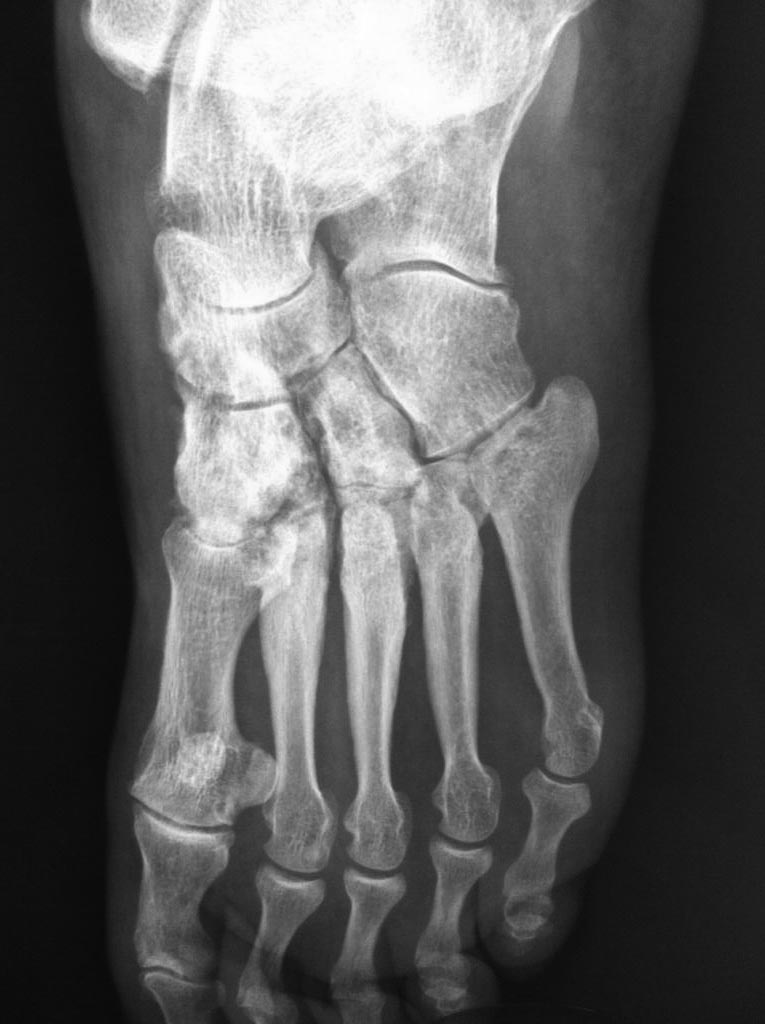

[Ortho] Асептический некроз костей среднего отдела стоп.

Доброго времени суток. Обратился пациент, 62 года, бытовые и трудовые

условия в данное время не отягощены и не были никогда тяжелыми, без

вредных привычек, со слов оперативных вмешательств не было, курсов

гормональной терапии не получал, периодически принимает лекарственные

препараты от арт. гипертензии. Без видимых причин около 1 года назад

появились боли в стопах при ходьбе и нагрузке, в связи с чем обратился к

ортопеду.

Лаб исследования: Ревмофактор, С-реакт. белок, АЦЦП, Мочевая кислота и

др. в пределах возрастной нормы. Хотелось бы услышать мнения. Заранее

благодарен.

Имя     : IMG_5003.jpg

Тип     : image/jpeg

Размер  : 72587 байтов

Описание: отсутствует

Url     : http://weborto.net:8080/pipermail/ortho/attachments/20141117/cf23b1b3/attachment-0004.jpg